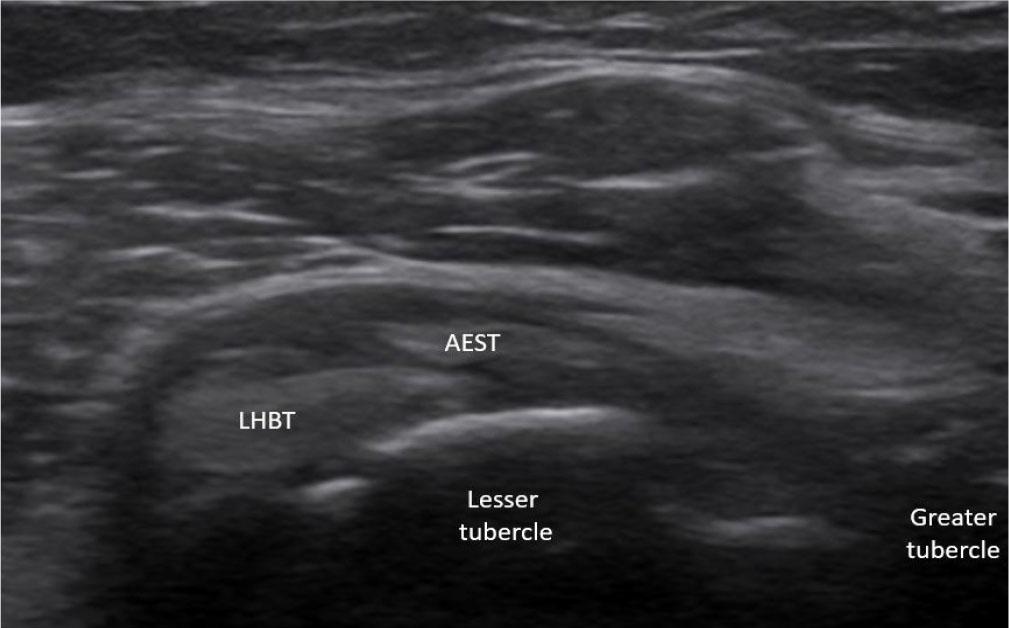

Aponeurotic expansion of the supraspinatus tendon (AEST) intragroove subluxation with preserved long head of the biceps tendon (LHBT) alignment in the right shoulder (AEST–LHBT classification: Ia, case 11)

The most frequent abnormality was AEST dislocation with preserved intragroove LHBT, observed in six of 19 cases (31.6%) (Fig. 15). LHBT dislocation in the presence of intragroove AEST was identified in three cases (15.8%) (Fig. 16), while AEST intragroove subluxation with preserved LHBT alignment was found in another three cases (15.8%) (Fig. 17). Combined pathology included two cases (10.5%) of concomitant AEST and LHBT dislocation (Fig. 18), one case (5.3%) of LHBT subluxation with intragroove AEST, and one case (5.3%) of concomitant AEST and LHBT subluxation (Fig. 19). In four cases (21.1%), no abnormalities were observed.